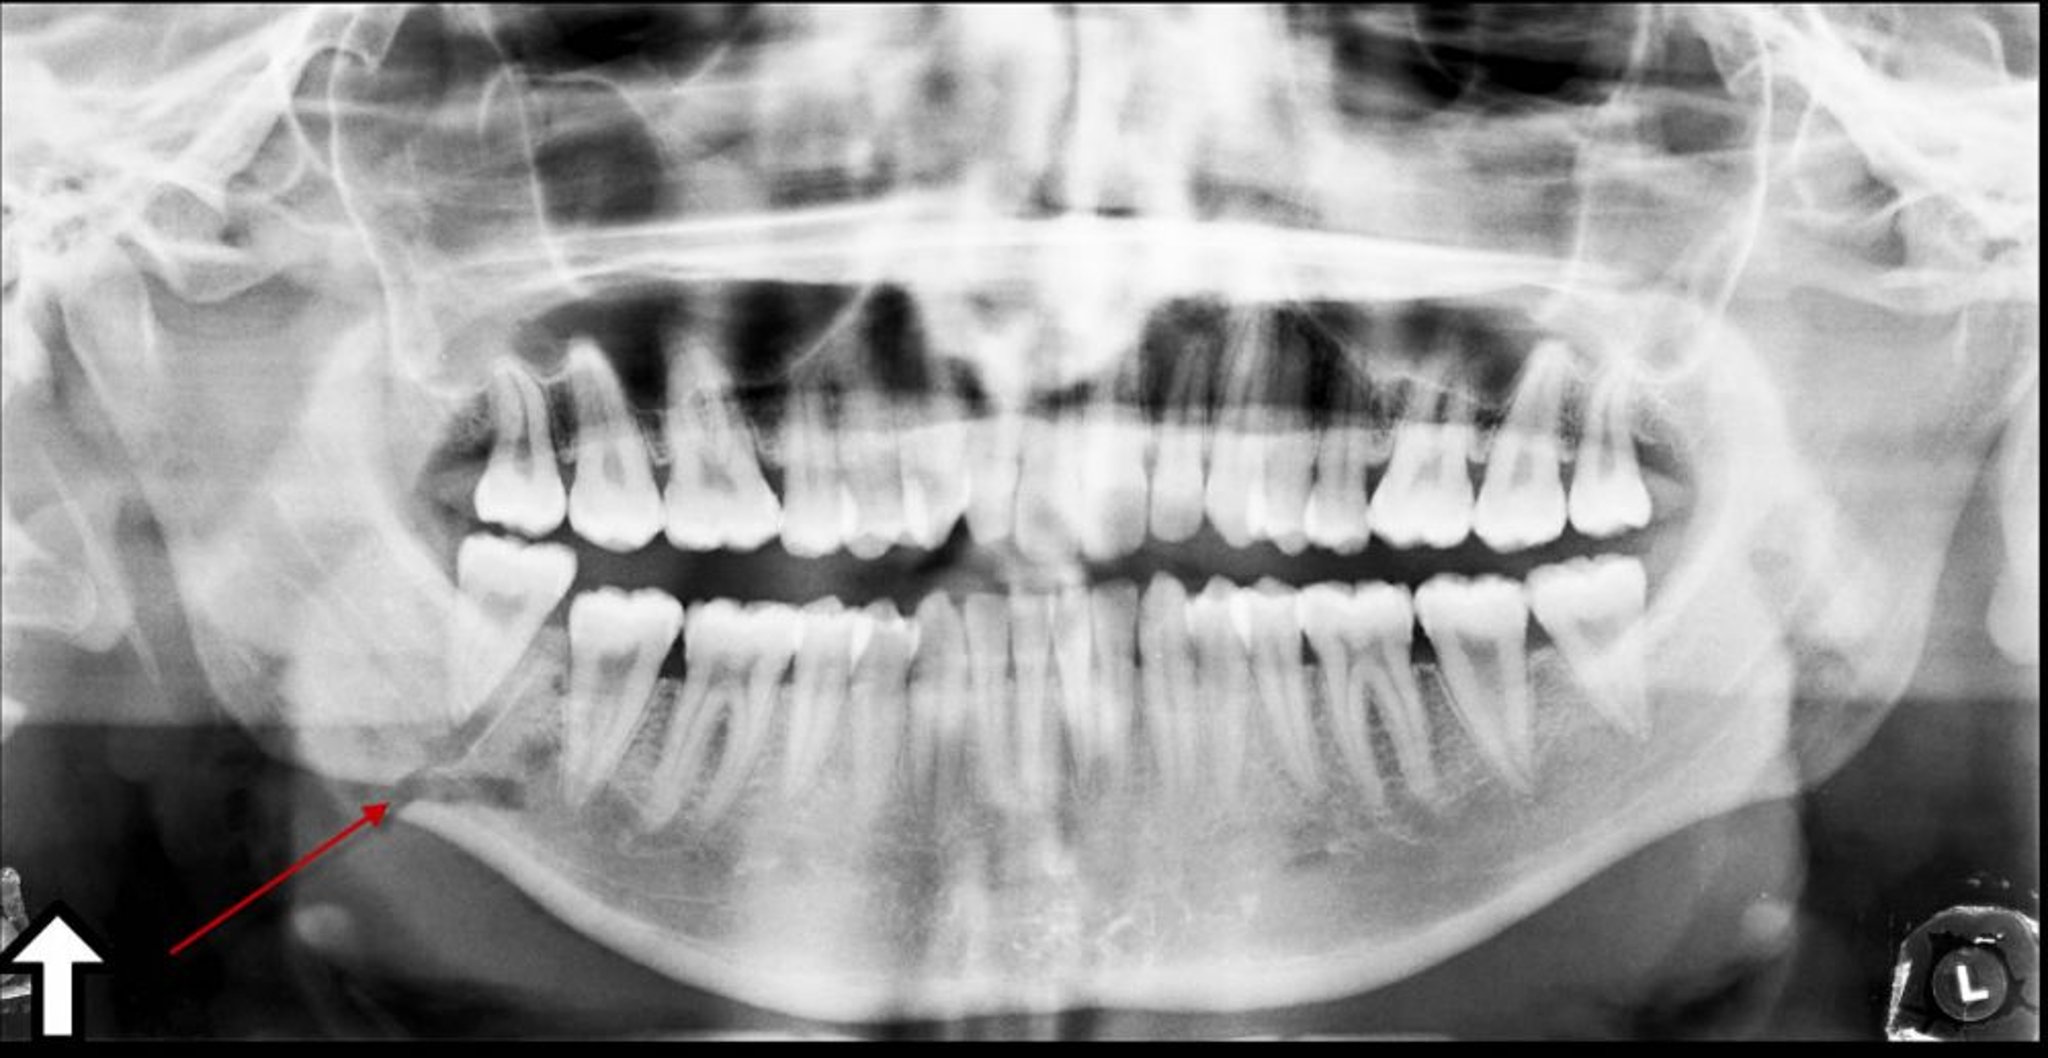

Эта панорамная рентгенонрамма показывает просветление (стрелка) под углом нижней челюсти, представляющие собой перелом.